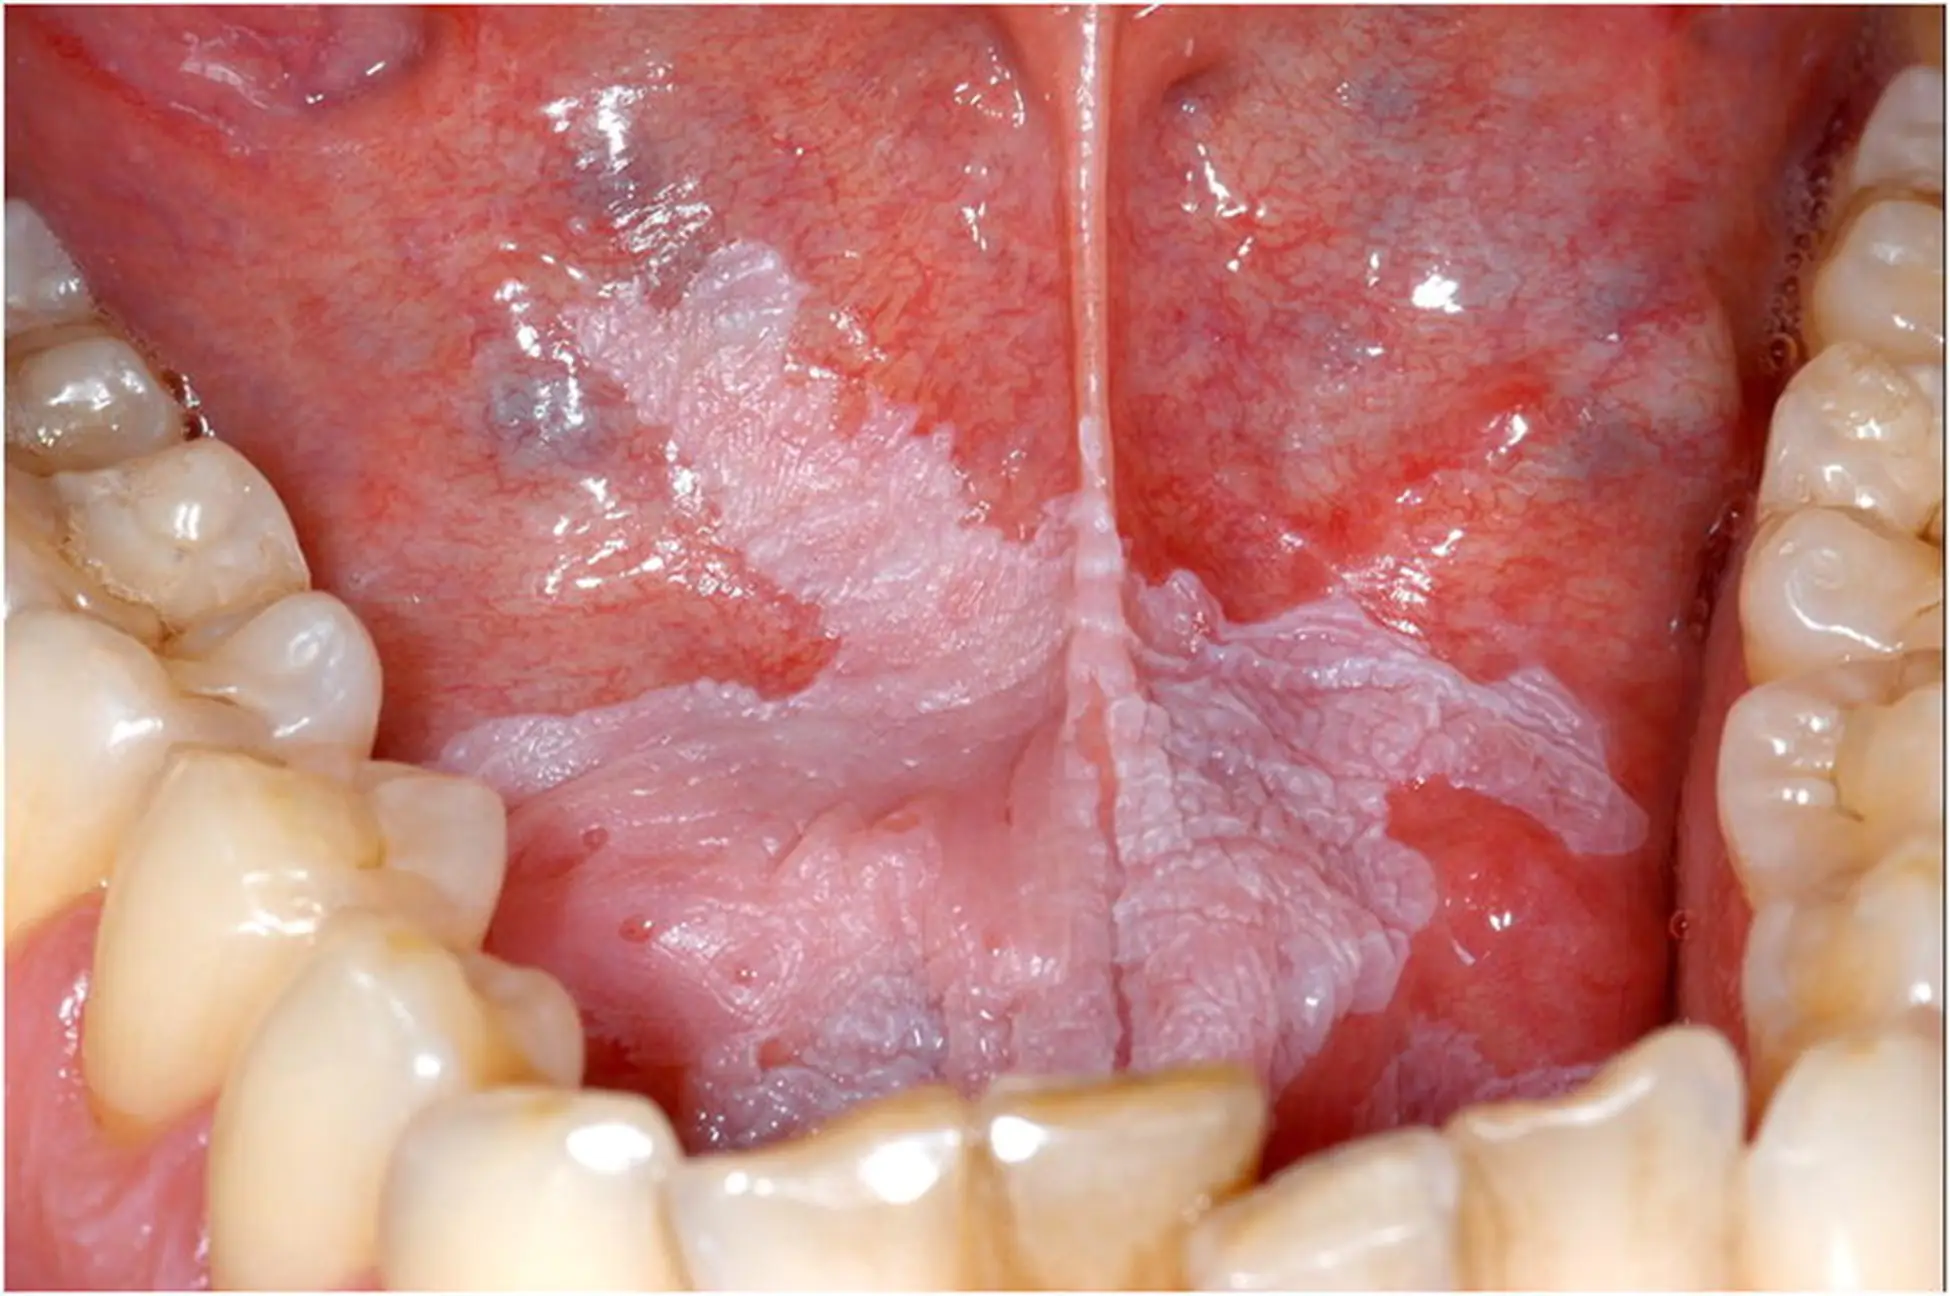

Leukoplakia is a white or gray patch that presents itself on the tongue, the inside of cheek, or on the floor of the mouth. It occurs as a result of the irritation of the mucous membranes of the mouth for a very long time. These patches may also present itself on the female genital area; however, the etiology of this lesion is not known yet.

These lesions may occur at any age but are most likely to be seen in older individuals. “Hairy” leukoplakia of the mouth is not commonly found form of leukoplakia which is thought to be caused by the Epstein-Barr virus, and occurs in individuals that were infected with HIV, have AIDS, or AIDS-related complex. It may present itself as thrush, an infection that is thought to be caused by a fungus Candida which occurs in induviduals who have a very low immunity and are susceptible to infections.

- White or gray in color

- Thick or slightly raised

- Hardened and rough in texture